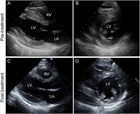

1. 心筋炎を疑ったら必ず心エコー検査を行う。患者における心機能評価や鑑別診断に役立つ(推奨度1)